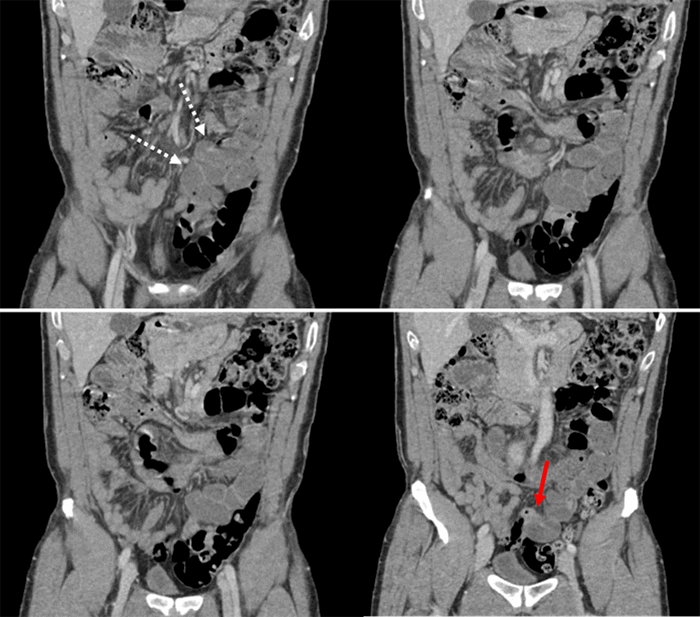

The patient is a 37-year-old male with no significant past medical history and no past surgical history who presented to the emergency department with a one-day history of severe, sharp, cramping epigastric pain with associated nausea and emesis. The patient did note similar episodes of abdominal pain one month prior that resolved spontaneously; he did not seek medical attention at that time. At presentation, he was afebrile and hemodynamically stable. Laboratory evaluations were unremarkable, including a normal white blood cell count without eosinophilia. A CT scan of the abdomen and pelvis was obtained with IV contrast, showing dilated loops of small bowel with suggestive transition point in the mid-small bowel. The radiologist also noted possible partial midgut malrotation and several prominent central mesenteric lymph nodes (Figure 1 and Figure 2). The patient was resuscitated with intravenous fluids, electrolyte repletion, and nasogastric decompression with plans for operation intervention. He improved clinically over the first night of hospitalization.

Figure 2. Coronal images from computed tomography scan of the abdomen and pelvis with IV contrast showing dilated loops of small bowel (dashed white arrows) and suspected transition point (solid red arrow).